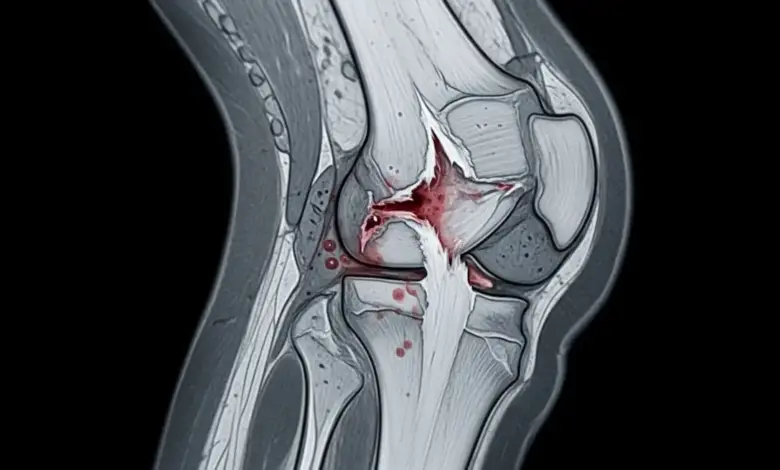

A radiografia ajuda a avaliar a posição da patela e excluir fraturas, e a ressonância é muito útil para confirmar a extensão da lesão e planejar o procedimento.

Portanto, fica claro que a imagem complementa o raciocínio clínico e ajuda no planejamento cirúrgico.